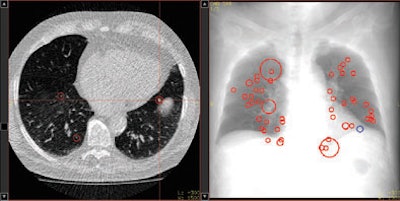

| Representative images of CT data analysis with CAD-2. The successful detection is presented in an axial maximum intensity projection (MIP) (upper left), in a thin-slice axial reconstruction (upper right), and as CAD marker in a coronal MIP (lower left), as well as in a volume-rendered view (lower right). |

Median false-positive rates per patient were five for CAD-1 versus six for CAD-2 with SD-CT. For ULD-CT, rates were eight for CAD-1 and three for CAD-2.

After separate statistical analysis of nodules with diameters of 5 mm and larger, detection rates increased to 83% for CAD-1 and 61% for CAD-2 at SD-CT and to 89% for CAD-1 and 67% for CAD-2 at ULD-CT. Overall, for both CAD systems, there were no significant differences between the detection rates for standard-dose and ultralow-dose datasets (p > 0.05).

Still, the number of false positives was highly variable by case, CAD system, and the use of standard or low-dose CT protocols.

"In case 21, CAD-1 found more than 25 false-positive nodules in a standard-dose CT scan," Romano said. "If we look at the ultra-low-dose results for CAD-2 [in the same case], there were absolutely no false-positive findings. In another example, there were more than 35 false-positive findings in CAD-1 in the ultra-low-dose dataset and only five false positives using standard dose for both CAD systems."

Differences between the systems could also be seen in the distribution of detected nodules, she said. "CAD-1 seemed to have more difficulties finding nodules close to the vessels, with 56% of the nodules missed," she said. CAD-2 had more difficulty finding nodules close to the pleural surface, with 42% missed nodules.